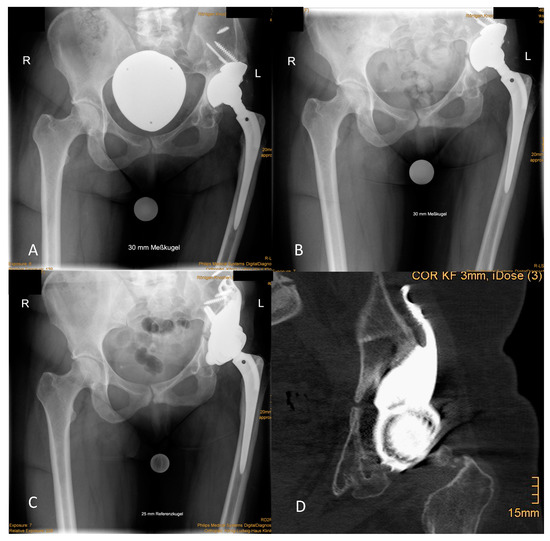

2.2. Implant

The CMAC is designed using data obtained via high-resolution CT imaging of the pelvis with an implant-specific algorithm (WinCad, Fa. AQ Solutions). Scans can be performed with or without a prosthesis or spacer in place. Figure 1 illustrates crucial templating steps that can be modified by the surgeon. After design approval by the surgeon, the implant is produced by laser melting of a titanium alloy (TiAI6V4) in a monoblock fashion with a 3D comb surface structure and with optional HA or CAP layering. The variability in form is reflected by Figures 1, 3 and 4. Manufacturing and delivering takes about 6 to 8 weeks.

Figure 1. Selected templating steps for a custom made monoflanged acetabular component (CMAC) with optional stem for intra- and extramedullary iliac fixation for a Paprosky IIIA defect: (A) Assessment and 3D visualization of the defect situation with and without subtraction of the implant. (B) CT-based estimation of leg length discrepancy (LLD) respecting pelvic tilt and joint contractures. (C) Virtual reconstruction of the hip center of rotation (COR) by positioning a standard acetabular component of a specific size at the anatomical COR. Bone that has to be reamed to position the original implant is colored in red. (D) Design features of the CMAC: The large segmental iliac defect is filled by the implant’s metallic monoblock assembled socket. Screws are positioned in areas of the pelvis that are characterized by intact host bone with a recommendation for their length in millimeters. For further primary stability, the surgeon can implant an additional intramedullary press-fit stem (entrance point colored in red). Planning and defect classification have previously been described in detail by our group (11).